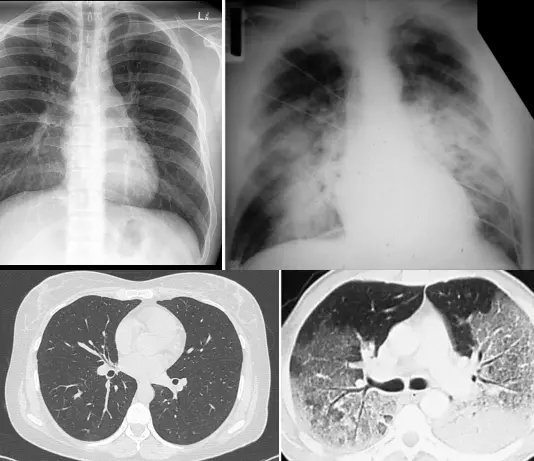

正常胸片/胸部 CT vs ARDS 图源:参考文献[2]

聊到白肺,不得不聊 ARDS。临床上,白肺一般指肺部大面积炎症所产生的影像学表现,具体表现为双肺浸润影,多见于急性呼吸窘迫综合症(acute respiratory distress syndrome, ARDS)。